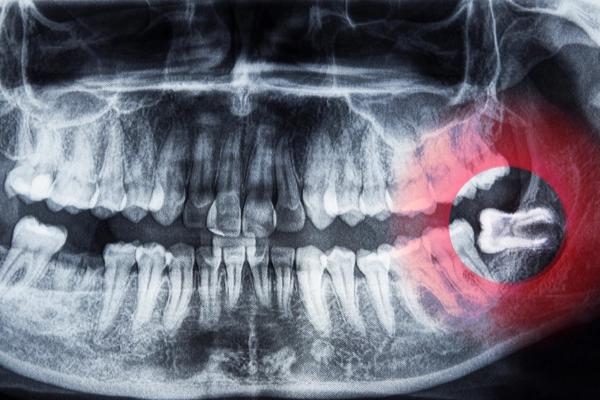

Kỹ thuật nhổ răng số 8 bằng máy siêu âm không đau, an toàn

Đau răng số 8 có nguy hiểm không? Bật mí cách giảm đau răng khôn hiệu quả